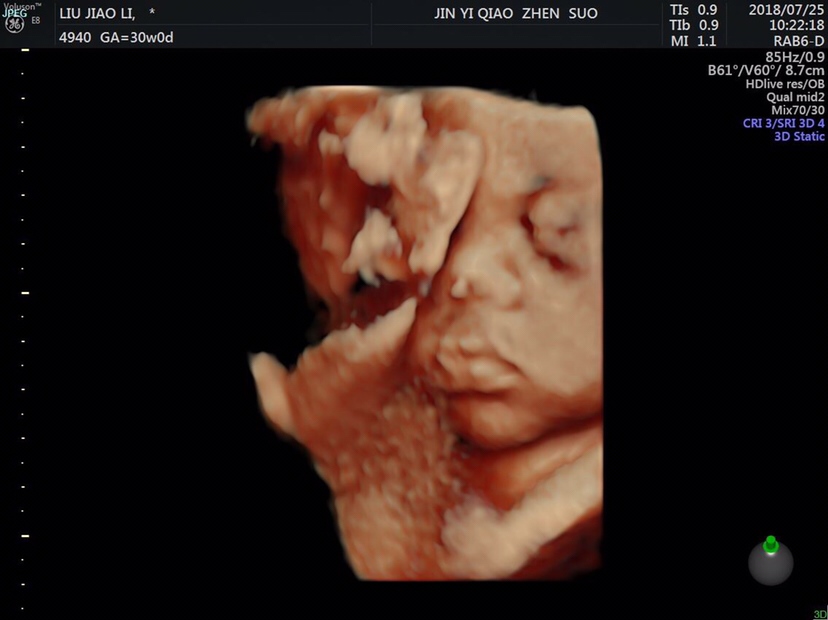

好可爱啊,和彩超里面一样的